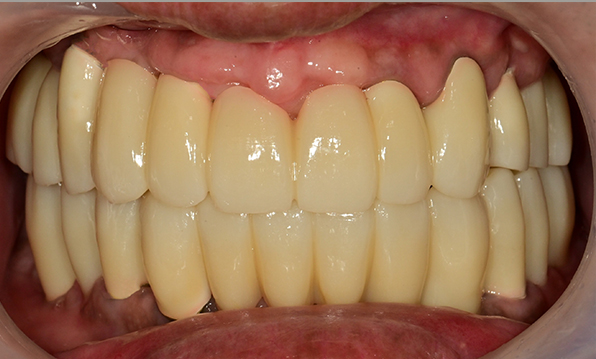

Case 01

Before After